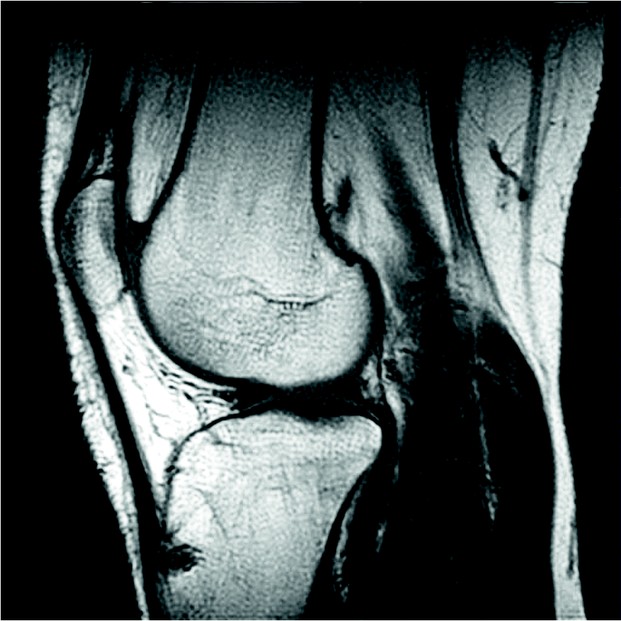

Невыраженный синовит коленного сустава диагностируют с помощью инструментальных методов. Рентген, УЗИ, МРТ позволяют выявить характерные изменения в суставе. Важным является биохимический анализ крови, особенно при диагностике синовита, вызванного ревматоидным артритом или иммунологическими нарушениями.